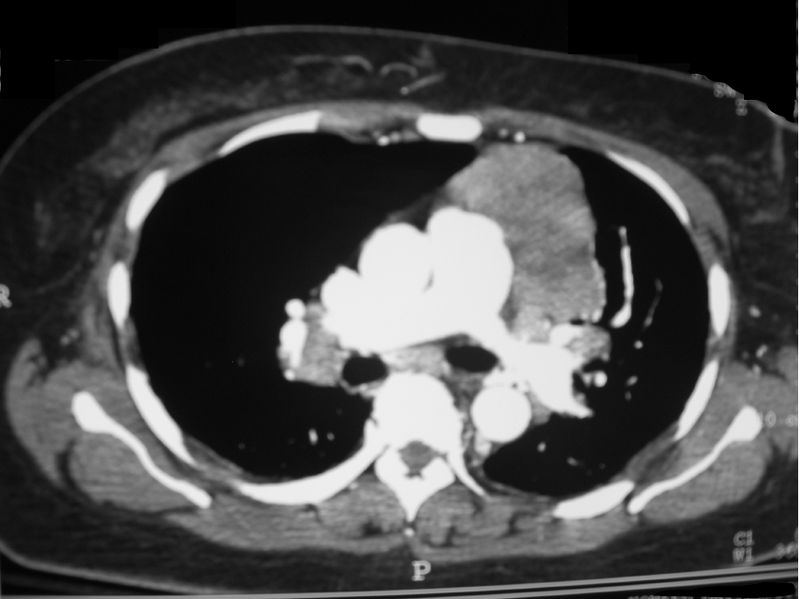

Thymectomy

Surgical removal of the thymus is usually recommended in patients who have a thymoma. A Thymectomy may also be beneficial in patients who develop the disease under 45 years of age, this is because in these patients the thymus is one of the places where the antibodies against the AChR are made. Following a thymectomy improvement of symptoms may become apparent after the first year usually however it can take upto three years. If the patient recovers or improves significantly following the operation they may not require additional therapy however in many cases patients need further treatment.

A-P Xray of Thyroma courtesy of Wikicommon under creative commons license